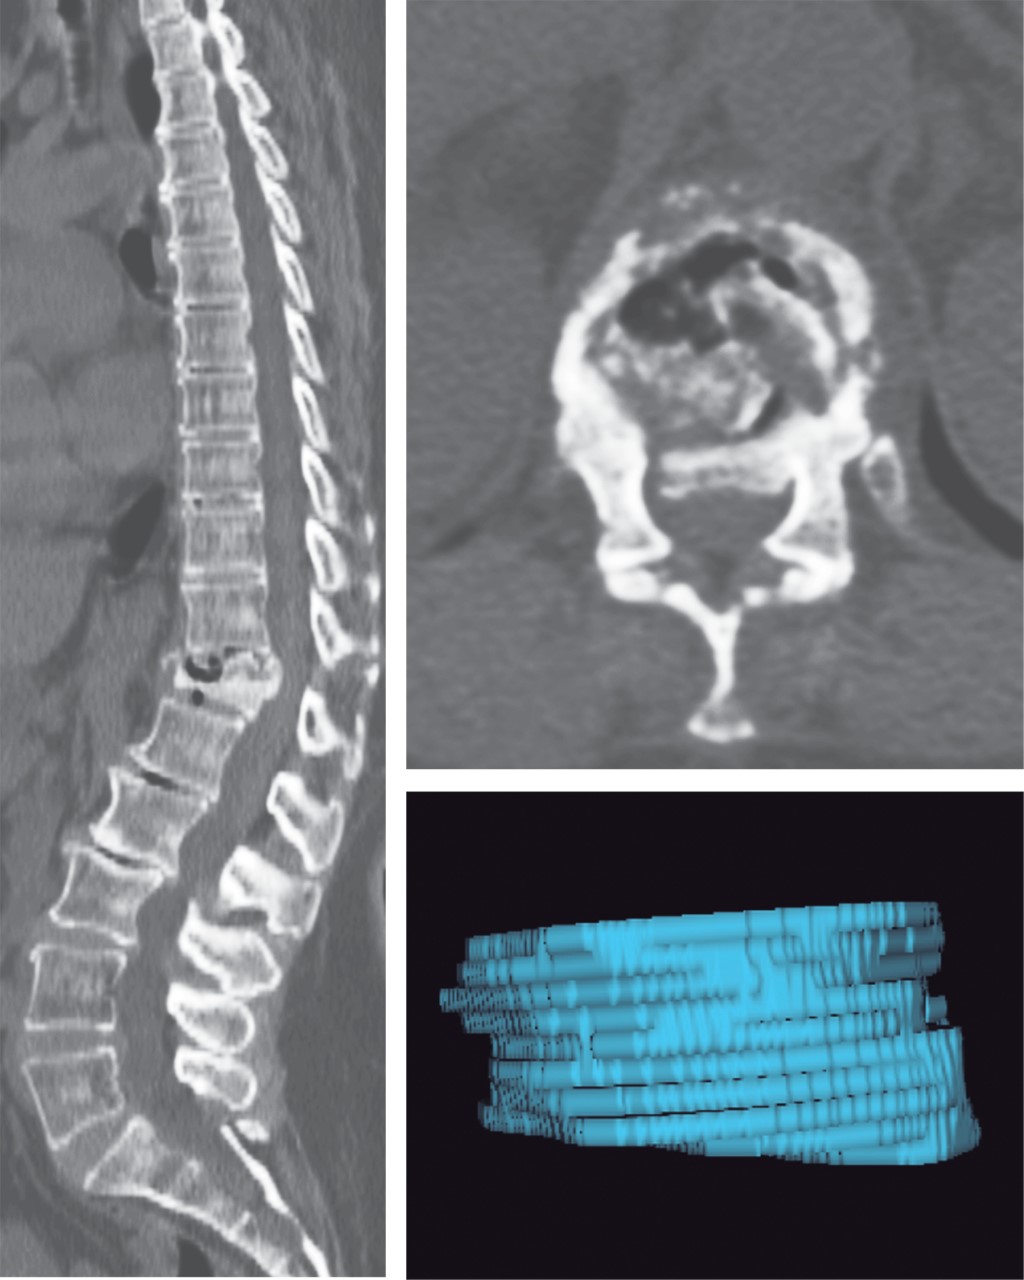

On physical examination, the patient presented axial pain of variable intensity on palpation of the dorsal region at the level of the spinous processes of T12 and L1. The motor system had a strength of 5/5 in all four limbs on the Daniels Modified Scale and preserved superficial and deep sensitivity. She had muscle stretch reflexes ++ globally and had no gait limitation. The rest of the neurological examination was normal (Figure 1).

A simple spine tomography was performed, where a compression fracture of the T12 vertebral body was observed, which was classified as a A3 type fracture according to the thoracolumbar spine injury classification system of the AO Foundation (Arbeitsgemeinschaft Osteosynthese). Additionally, volumetric reconstruction of the affected vertebral body was performed, obtaining a volume of 19.3476 cm3 (Figure 2).

Immediately after the procedure, a new spine tomography study was obtained, where a recovery in the anterior wall height of the affected vertebral body was observed. A new volumetric analysis of the vertebral body was then calculated, which turned out to be 21.0140 cm3, which represents a volume gain of 1.6664 cm3, which is equal to an increase of 8.6% compared to the previous height of the same vertebra (Figure 3 and Table 1).